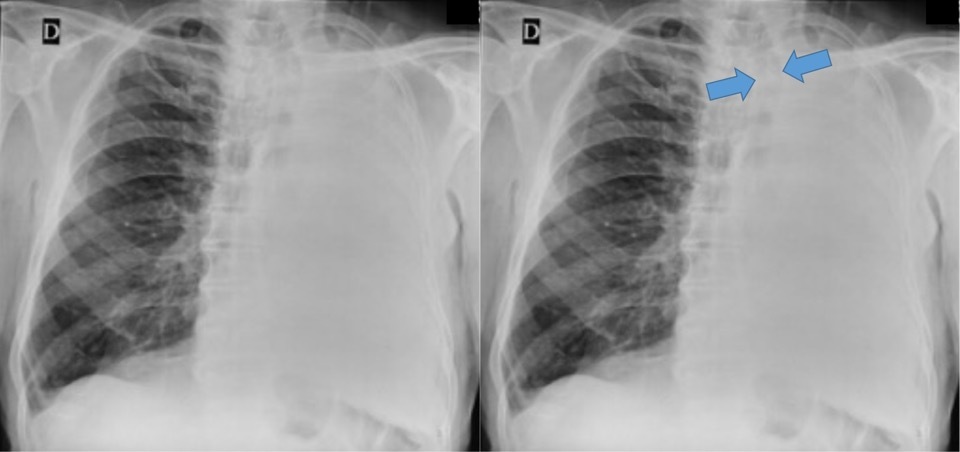

Classificação (Volume)

Tórax Opaco - Atelectasia

Tórax Opaco

DP

Derrame pleural bilateral.